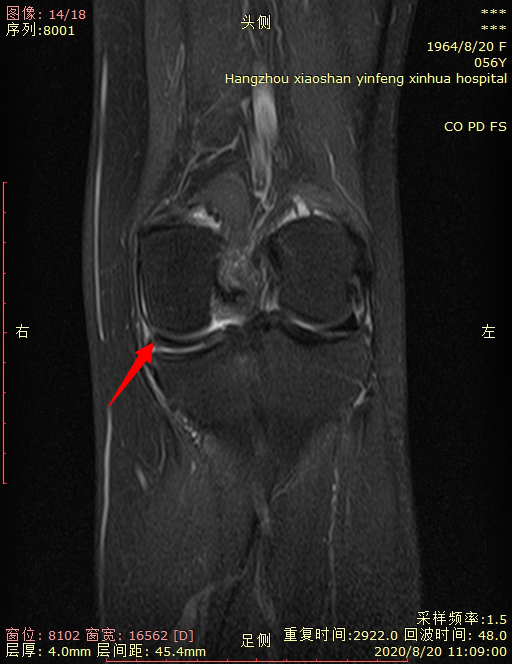

03 右膝关节半月板撕裂。